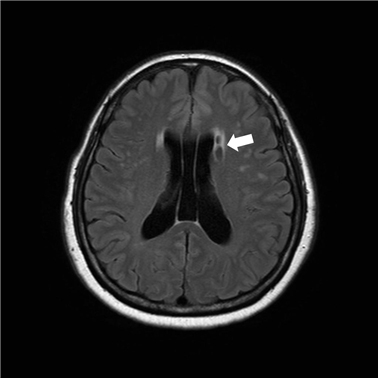

뇌경색 검사방법

우선 뇌경색 초기증상이 보인다면 내원을 하기에 전문가와 상담을 진행하게 되겠고, 진척되는 뇌경색 검사형식으로는 뇌혈관 자기 공명영상, 공명영상 촬영술, 전산화 단층 촬영, 심장 초음파, 경동맥 초음파, 뇌혈관 초음파 등의 방법으로 환자의 현재 상태를 터득해서 치료가 진행되겠습니다.

이 질병을 진단하는 검사로는 몇 가지가 연속될 수 있다고 합니다. 뇌졸중에는 뇌출혈과 뇌경색이 실재하는데, 이 양쪽 모두는 양상이 다르며 무엇이냐에 따라서 치료 절차도 상이하기 때문에 뇌경색 검사방법으로 진단을 정확히 받아서 확인하는게 선행되어야 하고 귀중가운데 하나이라고 할 수 있고요.